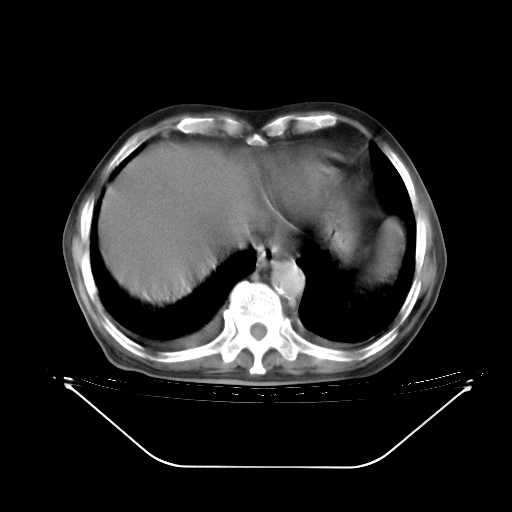

今天复查肺部CT,发现双肺广泛磨玻璃样改变。所以我把3月19日和5月9日相隔50天的肺部CT上传。请大家会诊。

2009年3月19日肺部CT片。

5月9日肺部CT(在4月27日齐鲁医院肺部CT描述部分肺组织磨玻璃样改变,12天后肺组织广泛磨玻璃样改变)